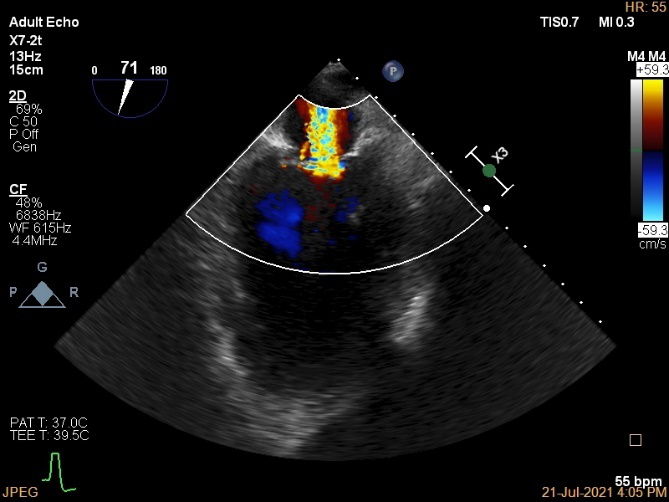

术前超声诊断:

长轴:左室下后壁节异,LAV:101ml,LVEDV:239ml

Bicom:MR(重度),返流束宽15.8mm,返流面积10.6cm²

3D-color MV view:血流主要来源于2区近3区

麻醉方式为全麻,建立静脉通路后,穿刺右侧股静脉,预埋ProGlide缝合器,食道超声指导下房间隔穿刺成功,鞘管扩张穿刺部位,沿导丝将导引导管送入左房,MitraClip调整后顺利到达二尖瓣目标位置,在X线及食道超声辅助下,将MitraClip NTR二尖瓣夹精确定位后,成功夹合二尖瓣A2-P2区,超声显示反流明显减少,多切面证实夹合组织充分,肺静脉多普勒波形由反向恢复正常,手术顺利结束,安返普通病房。

X-plane:下夹子尝试捕获2区

夹子逐渐夹闭后,2区返流逐渐减少